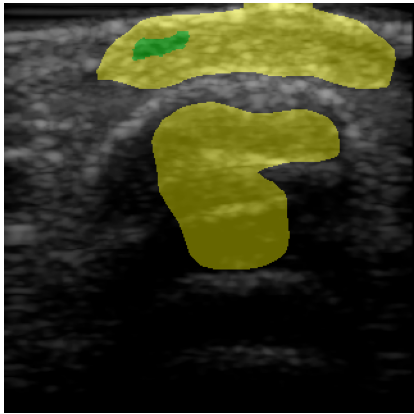

Chronic wounds including diabetic and arterial/venous insufficiency injuries have become a major burden for healthcare systems worldwide. Demographic changes suggest that wound care will play an even bigger role in the coming decades. Predicting and monitoring response to therapy in wound care is currently largely based on visual inspection with little information on the underlying tissue. Thus, there is an urgent unmet need for innovative approaches that facilitate personalized diagnostics and treatments at the point-of-care. It has been recently shown that ultrasound imaging can monitor response to therapy in wound care, but this work required onerous manual image annotations. In this study, we present initial results of a deep learning-based automatic segmentation of cross-sectional wound size in ultrasound images and identify requirements and challenges for future research on this application. Evaluation of the segmentation results underscores the potential of the proposed deep learning approach to complement non-invasive imaging with Dice scores of 0.34 (U-Net, FCN) and 0.27 (ResNet-U-Net) but also highlights the need for improving robustness further. We conclude that deep learning-supported analysis of non-invasive ultrasound images is a promising area of research to automatically extract cross-sectional wound size and depth information with potential value in monitoring response to therapy.